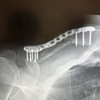

病名:右鎖骨骨折幹部骨折

術式:観血的整復固定術

・骨折観血的手術(鎖骨):113,700円

・手術材料

プレート(骨端用(生体用合金)標準型):76,000円

スクリュー(一般(生体用合金)):5,890円

骨折観血的手術と材料費が半々だということに驚きました。っていうか需要と供給でモノの価格は決まるとはいえ、チタンプレート高いなぁ。そして「手術」と「麻酔」は別の欄として表記されていて、いかに全身麻酔が手術において重要なものだとわかりました。寝て、起きたら手術が終わっていたからなぁ・・・。相変わらずDPCの詳細が良くわからないけれど、たぶん突っ込んでも仕方のないことなんでしょうね。